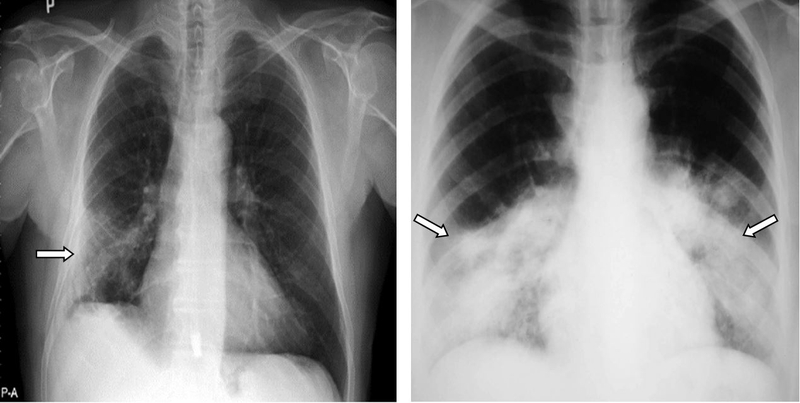

Tình trạng xơ hóa ở phổi có thể được nhìn thấy trên hình ảnh xơ trên phim CT scan hoặc trên mô bệnh học qua sinh thiết phổi. Đi kèm với chứng xơ phổi hậu covid là tình trạng giảm thể tích phổi và giảm độ khuếch tán của phổi qua các thăm dò chức năng hô hấp.